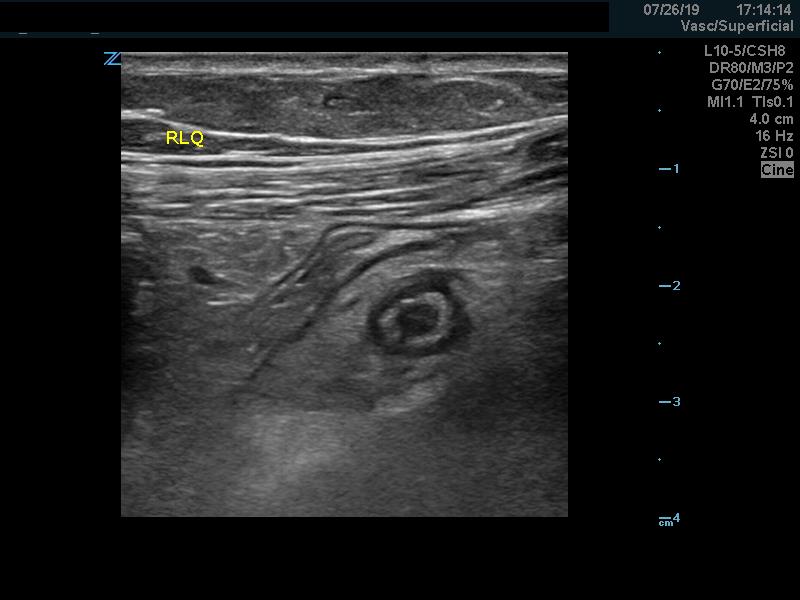

Diagnostic criteria: Appendix measuring more than 6 mm in transverse diameter under compression (98% Sens)1

Figure 5. Dilated, non-compressible appendix.

Video 3. Dilated, non-compressible appendix (compression applied).